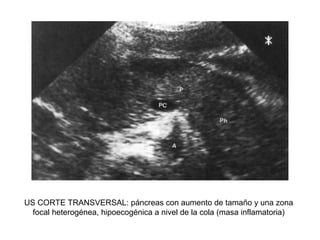

US CORTE TRANSVERSAL: páncreas con aumento de tamaño y una zona

focal heterogénea, hipoecogénica a nivel de la cola (masa inflamatoria)